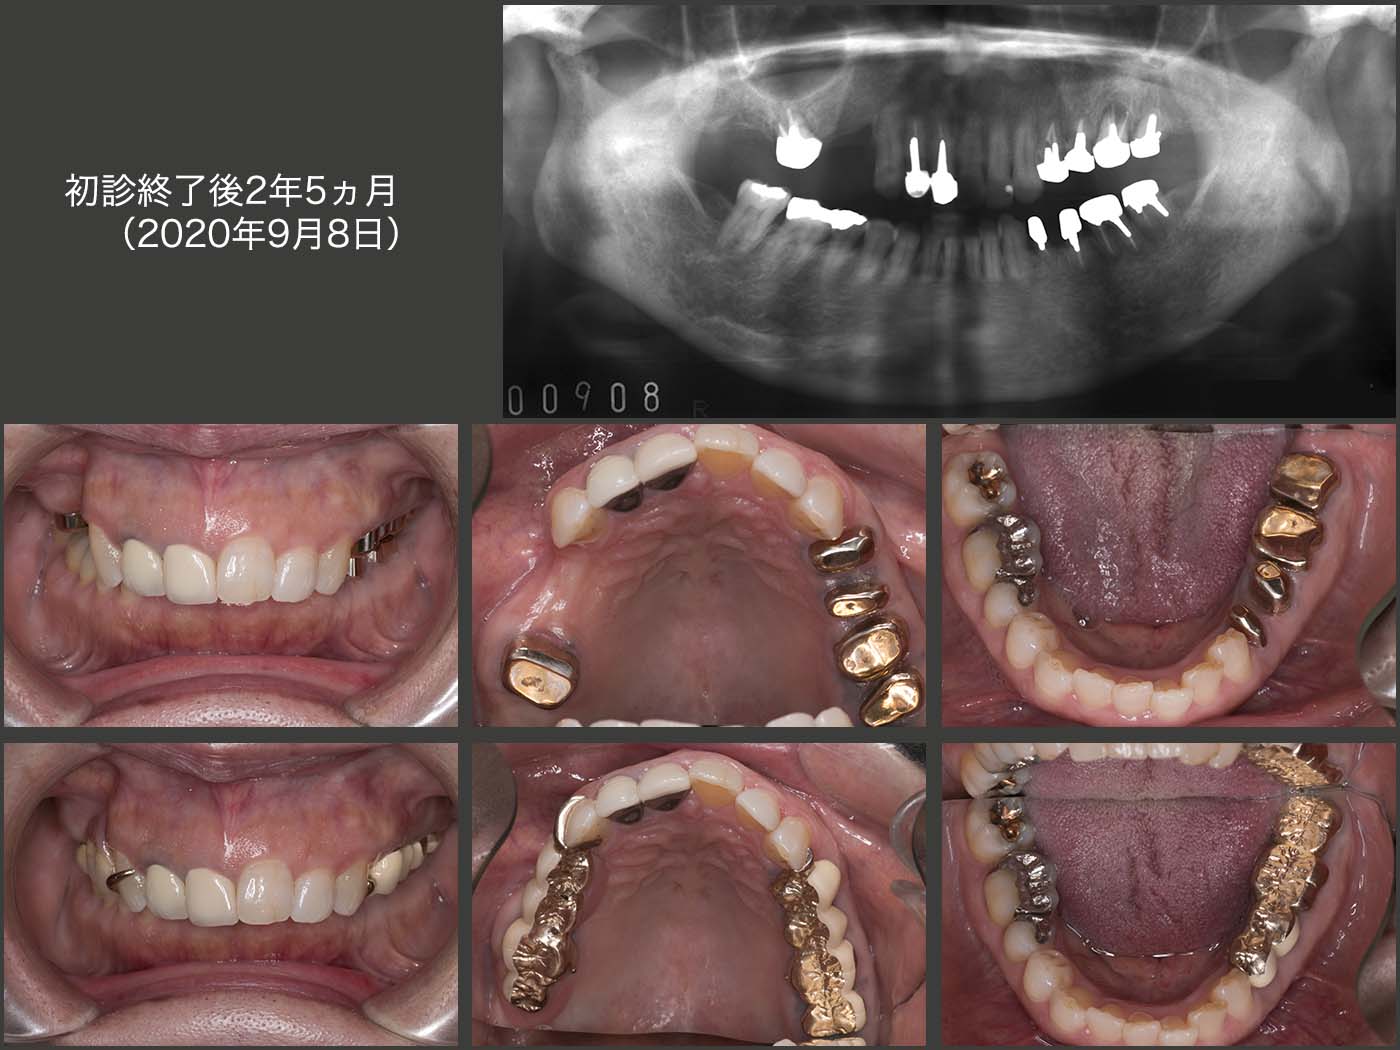

2018年4月,初診終了時の状態.右上については,即時義歯のままでも構わないが,咬合高径がない分,支台装置をくるむレジン量が少ないことが危惧された.そこで,義歯の破折を予防するために,さらに強固な義歯に作り換えた.(咀嚼の中心は左側のため,右側の義歯の破折は生じにくい.少々オーバートリートメントの感は拭えない.)

義歯を装着した状態.上下左側の個々の歯は当初条件が悪かったが,連結固定したことで咬合・咀嚼力に対応でき,また左側の咬合支持を強固に得られたことは,今後の経過によい影響を及ぼすであろうと期待している.ただ,左側の偏咀嚼および咬み過ぎによる歯根破折の問題もあるので,意識して右側でも咀嚼して貰うこと,また,あまり硬いものを左側で咬まないようにお願いしている.